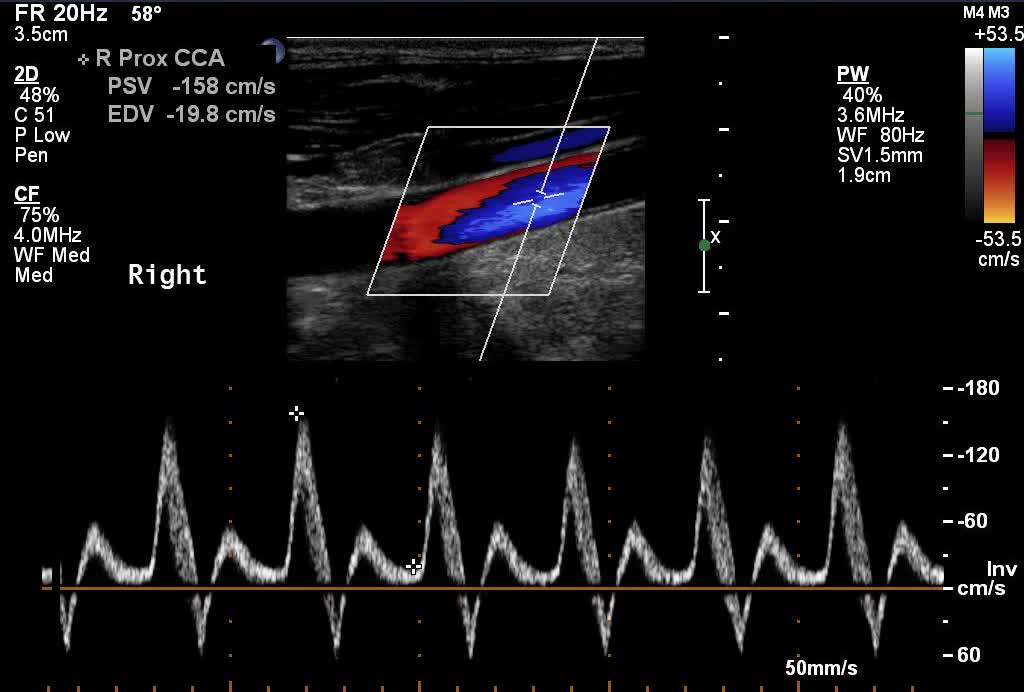

Ulteriore esame di secondo livello per escludere la presenza o meno di deficit vascolari è l'ecocolordoppler penieno in farmaco erezione, esame ecografico che si esegue dopo somministrazione di prostaglandine per via intracavernosa, dove si valutano i flussi sistolici e diastolici delle arterie cavernose.